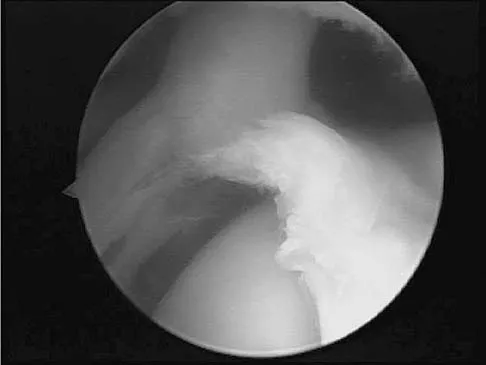

A baseball pitcher has intractable posterior and superior shoulder pain. The arthroscopic view seen in Figure 25 shows no Bankart or Hill-Sachs lesion and a negative drive-through sign. There are no signs of ligamentous laxity, but active compression and anterior slide tests are positive. Treatment should consist of

Explanation